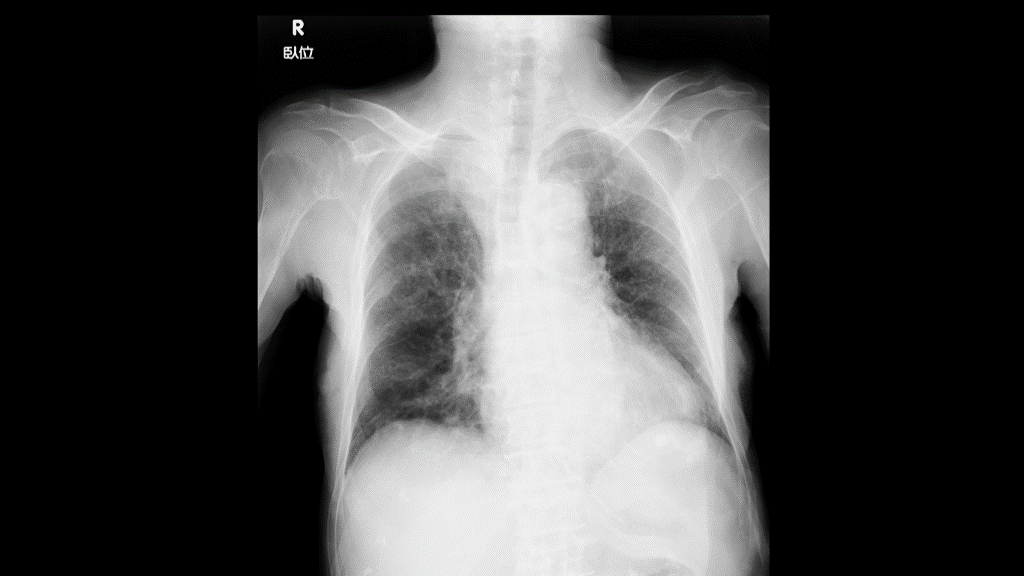

BP157/86mmHg, p 132/min, SpO2 99%(10L/min) reg, BT 38.7℃ E4V1M4 焦点の合わない開眼+, 痛みに弱々しく逃避 瞳孔は正円同大, 対光反射sluggish,人形の目現象正常  項部硬直なし 心雑音なし 呼吸音静 腹部にあきらかな圧痛はなさそう 両側hand drop+ 筋緊張亢進・不随意運動なし Babinski上向き?(再現性なし) 尿道カテーテル留置すると、白色混濁尿が大量に流出